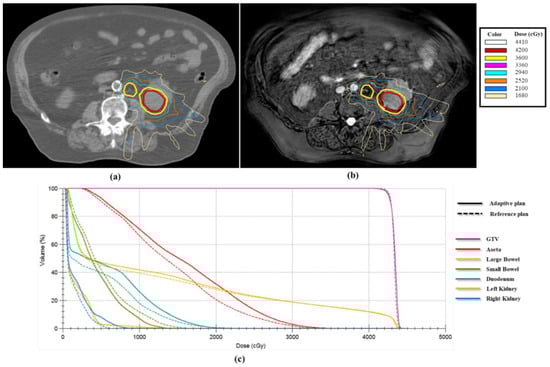

3.1. Adaptive Plan and Treatment Delivery

3.2. Motion Management with the Compression Belt